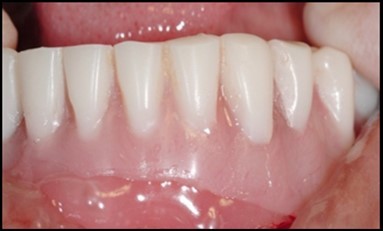

A transferable mark with an indelible pencil is placed on top of each ball abutment and old denture is seated to ideally determine the location for attachment housings. It is followed by preparation of recesses in the intaglio surface of the denture to accommodate the housings (Figure 7B). Lingual vent holes are made for escape of excess acrylic. Placement of nylon processing insert into each of the housings is done with insert seating tool. Figure 8 Seating of the attachment housing onto each ball type abutment is done (Figure 9). Undercuts are blocked out under the housing and soft tissue to prevent acrylic resin from locking the denture onto the abutment. Application of self curing acrylic is done into recessed area and around titanium housings for bonding of the housings to denture. Insertion of denture was done and guiding the patient into proper occlusion with the opposing arch. After the curing of acrylic, denture is removed. Excess acrylic is removed around the housings and lingual vent hole later it is polished (Figure 10). Replace nylon retention insert instead of processing insert into the housings. The insert must seat securely in place and be in level with the housings rim. Overdenture is seated over the ball abutments (Figure 11). Proper instructions have been given to the patient on insertion and removal of prosthesis (Figure 12). The patient was recalled at 1 week, 3 weeks, 3 months, 6 months follow up appointments.

General criteria for survival and success of implants have been used to evaluate the efficacy of immediately loading mandibular implants. For example, survival criteria include how the implant performs, particularly regarding the absence of pain, infection, and paresthesia. Implant immobility and the absence of periimplant radiolucency under radiography are 2 more criteria of implant survivability.6, 7 Success criteria include the additional element of absence of vertical bone loss; specifically, less than 1 mm during the first year and less than 0.2 mm annually thereafter. Granted that success rates for immediatel oading of implants in the edentulous mandible are not as high as rates for the traditional 2-stage approach, conditions nevertheless often warrant the 1-stage surgical option described here.7, 8, 9 (Figure 12).

Using 2 implants and retentive anchors for the retention of a mandibular complete denture is, in terms of immediate costs, one of the most affordable implant procedures. 8, 9, 14 With ideal placement of the implant, the stability of the prosthesis is excellent and the lingual dimensions of the denture can in some cases be reduced to the level of mylohyoid line, providing more space for the tongue and greater comfort than with conventional complete dentures.8, 9, 10, 15 However, if the labial musculature is tense or the amount of attached gingiva is limited, the implants should not be placed too deep or too labially, which might prevent gingival growth over the abutments. In those cases, ball anchor abutments with elevated shoulders can be used to improve implant anatomy.8, 9, 10 (Figure 12).